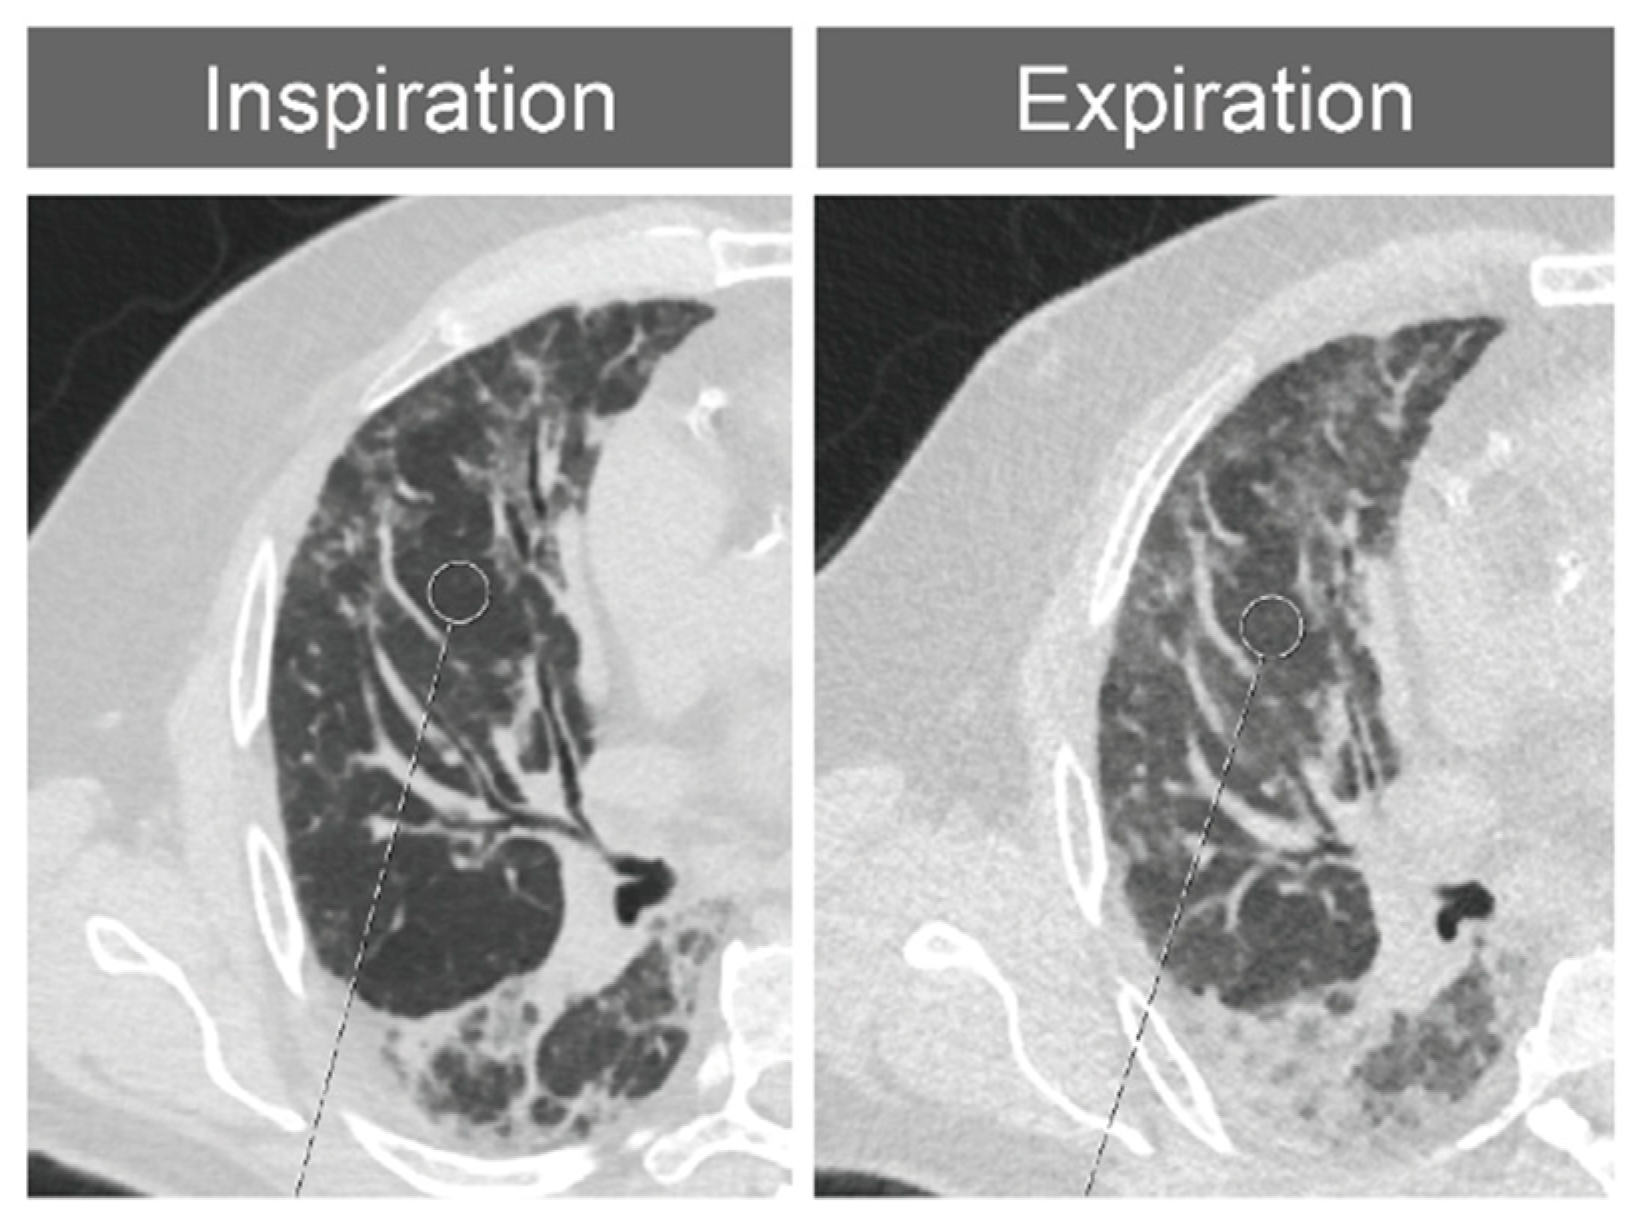

2.2. Thorax CT and Imaging Modalities

2.3. Segment-Based CT Densitometry

2.4. Expansion Measurements